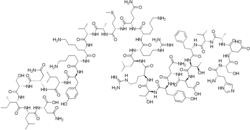

| Formula | C147H237N43O43S |

| Molar mass | 3326.83 g·mol−1 |

Vasoactive intestinal peptide (VIP) is a 28-residue amino acid peptide first characterized in 1970 that was initially isolated from porcine duodenum. A member of the secretin/glucagon hormone superfamily, VIP was initially discovered owing to its potent vasodilatory effects (as its name implies). VIP is widely distributed in the central and peripheral nervous system as well as in the digestive, respiratory, reproductive, and cardiovascular systems as a neurotransmitter and neuroendocrine releasing factor. These effects contribute to an extensive range of physiological and pathological processes related to development, growth, and the control of neuronal, epithelial, and endocrine cell function.[12]